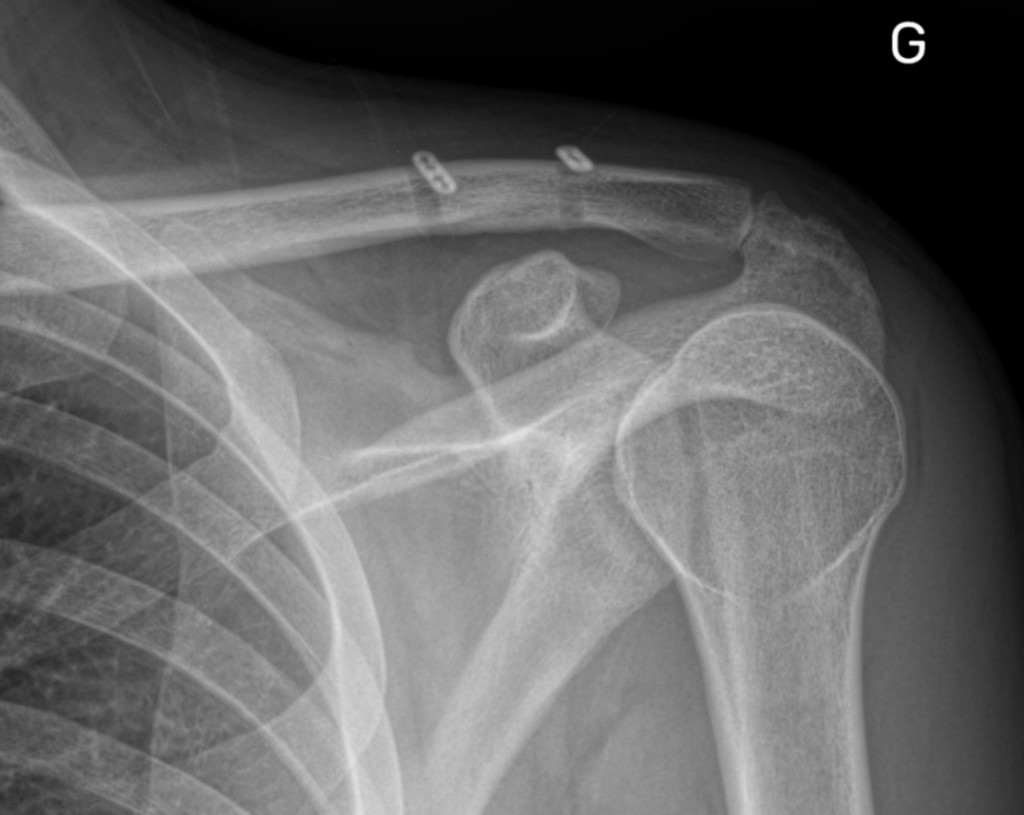

Le diagnostic implique un examen clinique où le médecin effectuera une palpation pour rechercher la douleur et évaluer la mobilité de l’articulation et de la clavicule. Des examens d’imagerie, tels que des radiographies de face et de profil, scanner, sont utilisés pour confirmer le diagnostic et évaluer la gravité de la luxation.

L’intervention consiste à placer des petites plaquettes métalliques reliées entre elles par des fils à haute résistance, pour réduire la luxation (double bouton arthroscopique).

Dans les cas chroniques, ou après échec de traitement médical, il est nécessaire d’associer au double bouton une ligamentoplastie (comme pour le ligament croisé du genou). Cette intervention, dite de Weaver Dunn Chuinard, a été le sujet de thèse du Dr Gastaud, et a fait l’objet de multiples publications scientifiques.